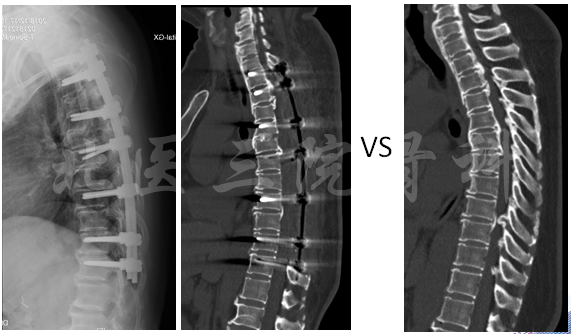

术前术后对比

诊断:胸椎管狭窄症,T1-6/T8-9后纵韧带骨化,T2-11黄韧带骨化;

手术方案:A.一起后路;B.T1-11椎管后壁切除;C.T4-5环形减压加+去后凸。